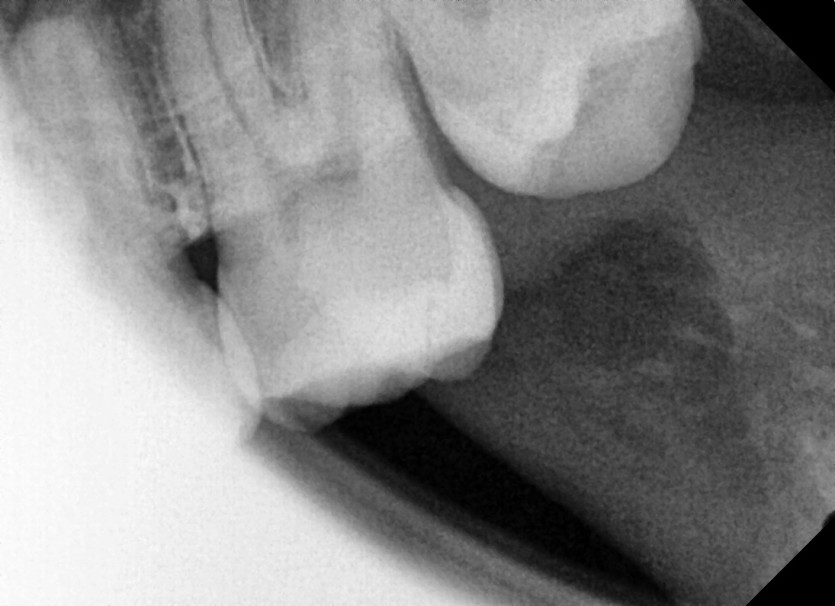

#28 사랑니 발치

구강 외과 전문의가 당일 발치했습니다.-----------------------------------------------------------------------------------------------------------------------------------